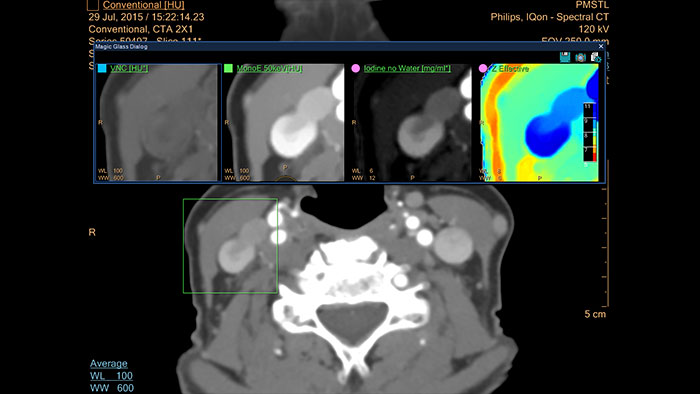

Spectral Light Magic Glass

CT Spectral Light Magic Glass

Review spectral data in a range of not spectral-enhanced CT applications

Allows retrospective use of spectral data that was saved in a series of spectral base images (SBI).

The fast launch of LMG allows review and identification of the most relevant results to be launched into the application for further analysis.

Benefits

• The option is available from the following applications: Brain Perfusion, Functional CT, Liver Analysis, PAA, TAVI, Acute Multifunctional Review, Virtual Colonoscopy.

• Spectral Magic Glass can be launched only for CT images or images created on the Philips IQon Spectral CT.

Spectral Magic Glass on PACS

CT Spectral Magic Glass on PACS*

IQon Spectral CT Functionality

IQon Spectral CT is the only scanner to offer CT Spectral Light Magic Glass and CT Spectral Magic Glass on PACS, helping radiologists review and analyze multiple layers of spectral data at once, including on their PACS.

• On-demand simultaneous analysis of multiple spectral results for an Region Of Interest (ROI).

• Integrates into a health system’s current PACS setup for certain PACS vendors.

• Spectral results viewable, during a routine reading.

• Enterprise-wide spectral viewing and analysis allows access to capabilities virtually anywhere in the organization.

* Standard with the CT Spectral option on IntelliSpace Portal.